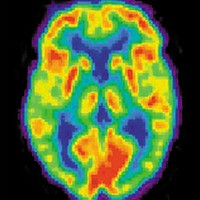

Drug abuse is probably linked to an in-built tendency to act without thinking, as shown by studies of siblings of chronic stimulant users, a leading neuroscientist will claim this week. Drawing on his research, Professor Trevor Robbins will argue that the risk-taking behaviour seen in drug abusers is not, as often thought, the result of drug-induced impaired brain function but instead is a factor that predisposes to drug taking in the first place. Speaking on 19 March at the University of Cambridge Science Festival (www.cam.ac.uk/sciencefestival), the UK's largest free science festival, he will also argue that cognitive-enhancing drugs that boost brain activity may have a place in treating certain diseases or in improving performance in occupations such as shift workers or surgery. "The fact that drugs can produce mind-altering effects through chemical activity has been known for centuries," explained Professor Robbins, who is Director of the Behavioural and Clinical Neuroscience Institute and head of the Department of Experimental Psychology. "But we now understand a great deal about how entire pharmacological classes of drugs exert their influence on the brain, for good and bad, and how our genetic make-up can modulate this activity." Most drugs of abuse target the reward system in the brain. There are literally dozens of brain chemicals called neurotransmitters that modulate the activity of brain cells, and drugs are capable of mimicking or stimulating these pathways.